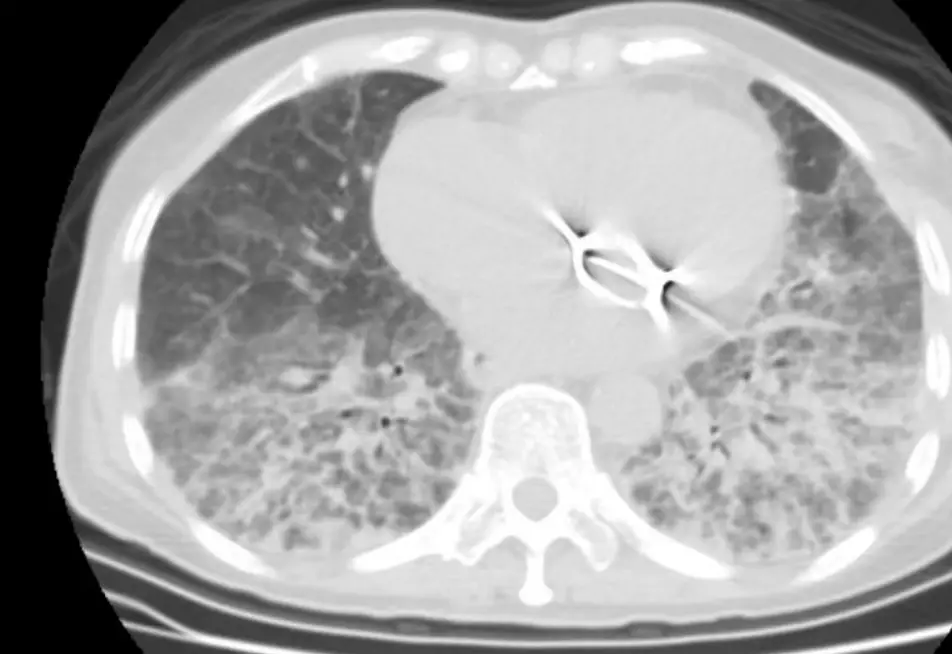

圖一(胸部 X 光,正面): 雙側肺野可見瀰漫性網狀-線條狀(reticular-linear)浸潤,以中下肺野為著,右側稍重於左側。可見明顯的間質性增厚線條,符合 Kerley B line 樣外觀,但分布更瀰漫,延伸至全肺野,不像單純心因性肺水腫侷限在下肺野。心臟左側可見金屬人工瓣膜(mechanical heart valve)的顯影縫環,符合病史中的二尖瓣換瓣手術。無局部實變(consolidation)、無明顯空洞或粟粒狀小結節。整體影像提示瀰漫性間質性病變而非局部感染。